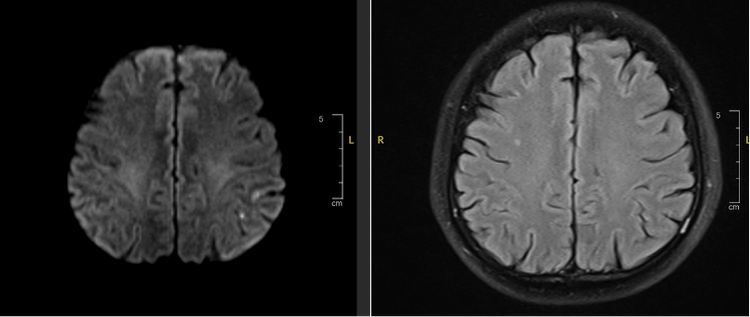

| Hình ảnh Mismatch trên xung DWI và FLAIR của bệnh nhân N.V.Đ - Ảnh BVCC |

Từ kết quả chụp MRI của 2 bệnh nhân, cho thấy có sự bất tương xứng (có Mismatch) giữa xung DWI và FLAIR (Hình 1 và Hình 3). Do đó trong 2 trường hợp này, sau khi hội chẩn bệnh nhân vẫn có chỉ định điều trị bằng thuốc tiêu huyết khối (rTPA) nhằm tái thông lại mạch máu đang tắc nghẽn.